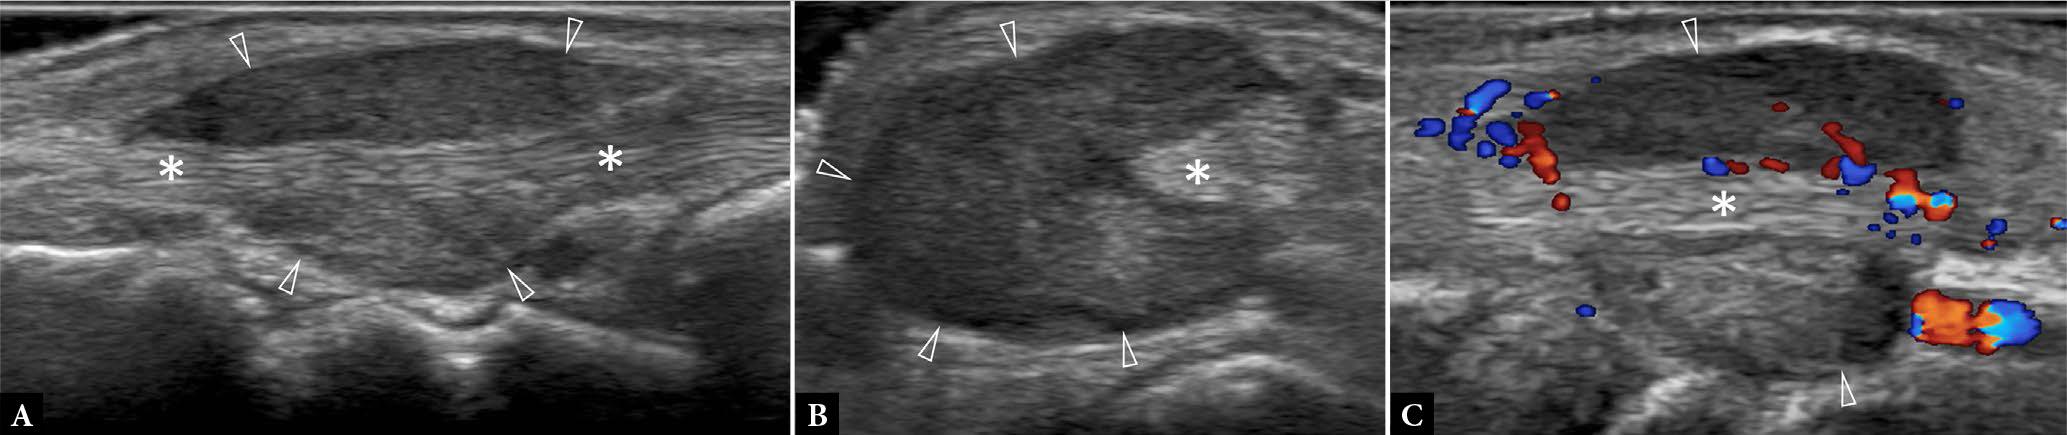

Fig. 10.

76-year-old female with a self-palpated nodular calf swelling slowly enlarging for one year. A. Longitudinal and B. transverse color Doppler US show a lobulated hypoechoic medium-sized (1.6 mm long × 0.8 mm deep × 3.0 cm wide) subcutaneous mass (*), in contact with, but not extending through, the investing fascia (arrowheads). C. Color Doppler US shows no demonstrable tumor vascularity. Either a solitary fibrous tumor or, less likely, plexiform neurofibroma, or a conglomerate of thrombosed varicose veins were considered the most likely diagnoses. Three months later, excisional biopsy was performed. Histology revealed myxoid dermatofibrosarcoma protuberans. Although the tumor margins were clear, wide local excision of the surgical bed was performed four months later. Three years later, the patient is well, with no evidence of recurrence